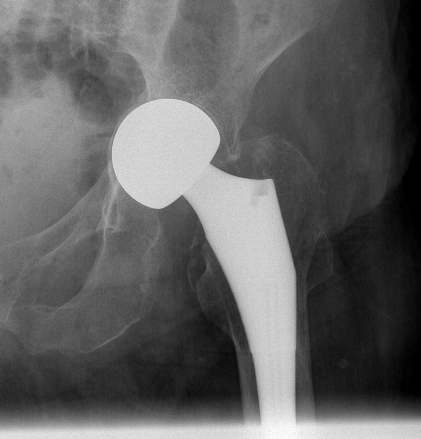

Unipolar

- single articulation between prosthesis and acetabulum

Unipolar monoblock

- Austin Moore press fit

- Thompson cemented

- no offset options

Austin Moore Thompson

Modular unipolar

Based on standard THR concepts

- alternative offset options

- neck length options

- cemented or uncemented

Cemented unipolar hemiathroplasty Uncemented bipolar hemiarthroplasty